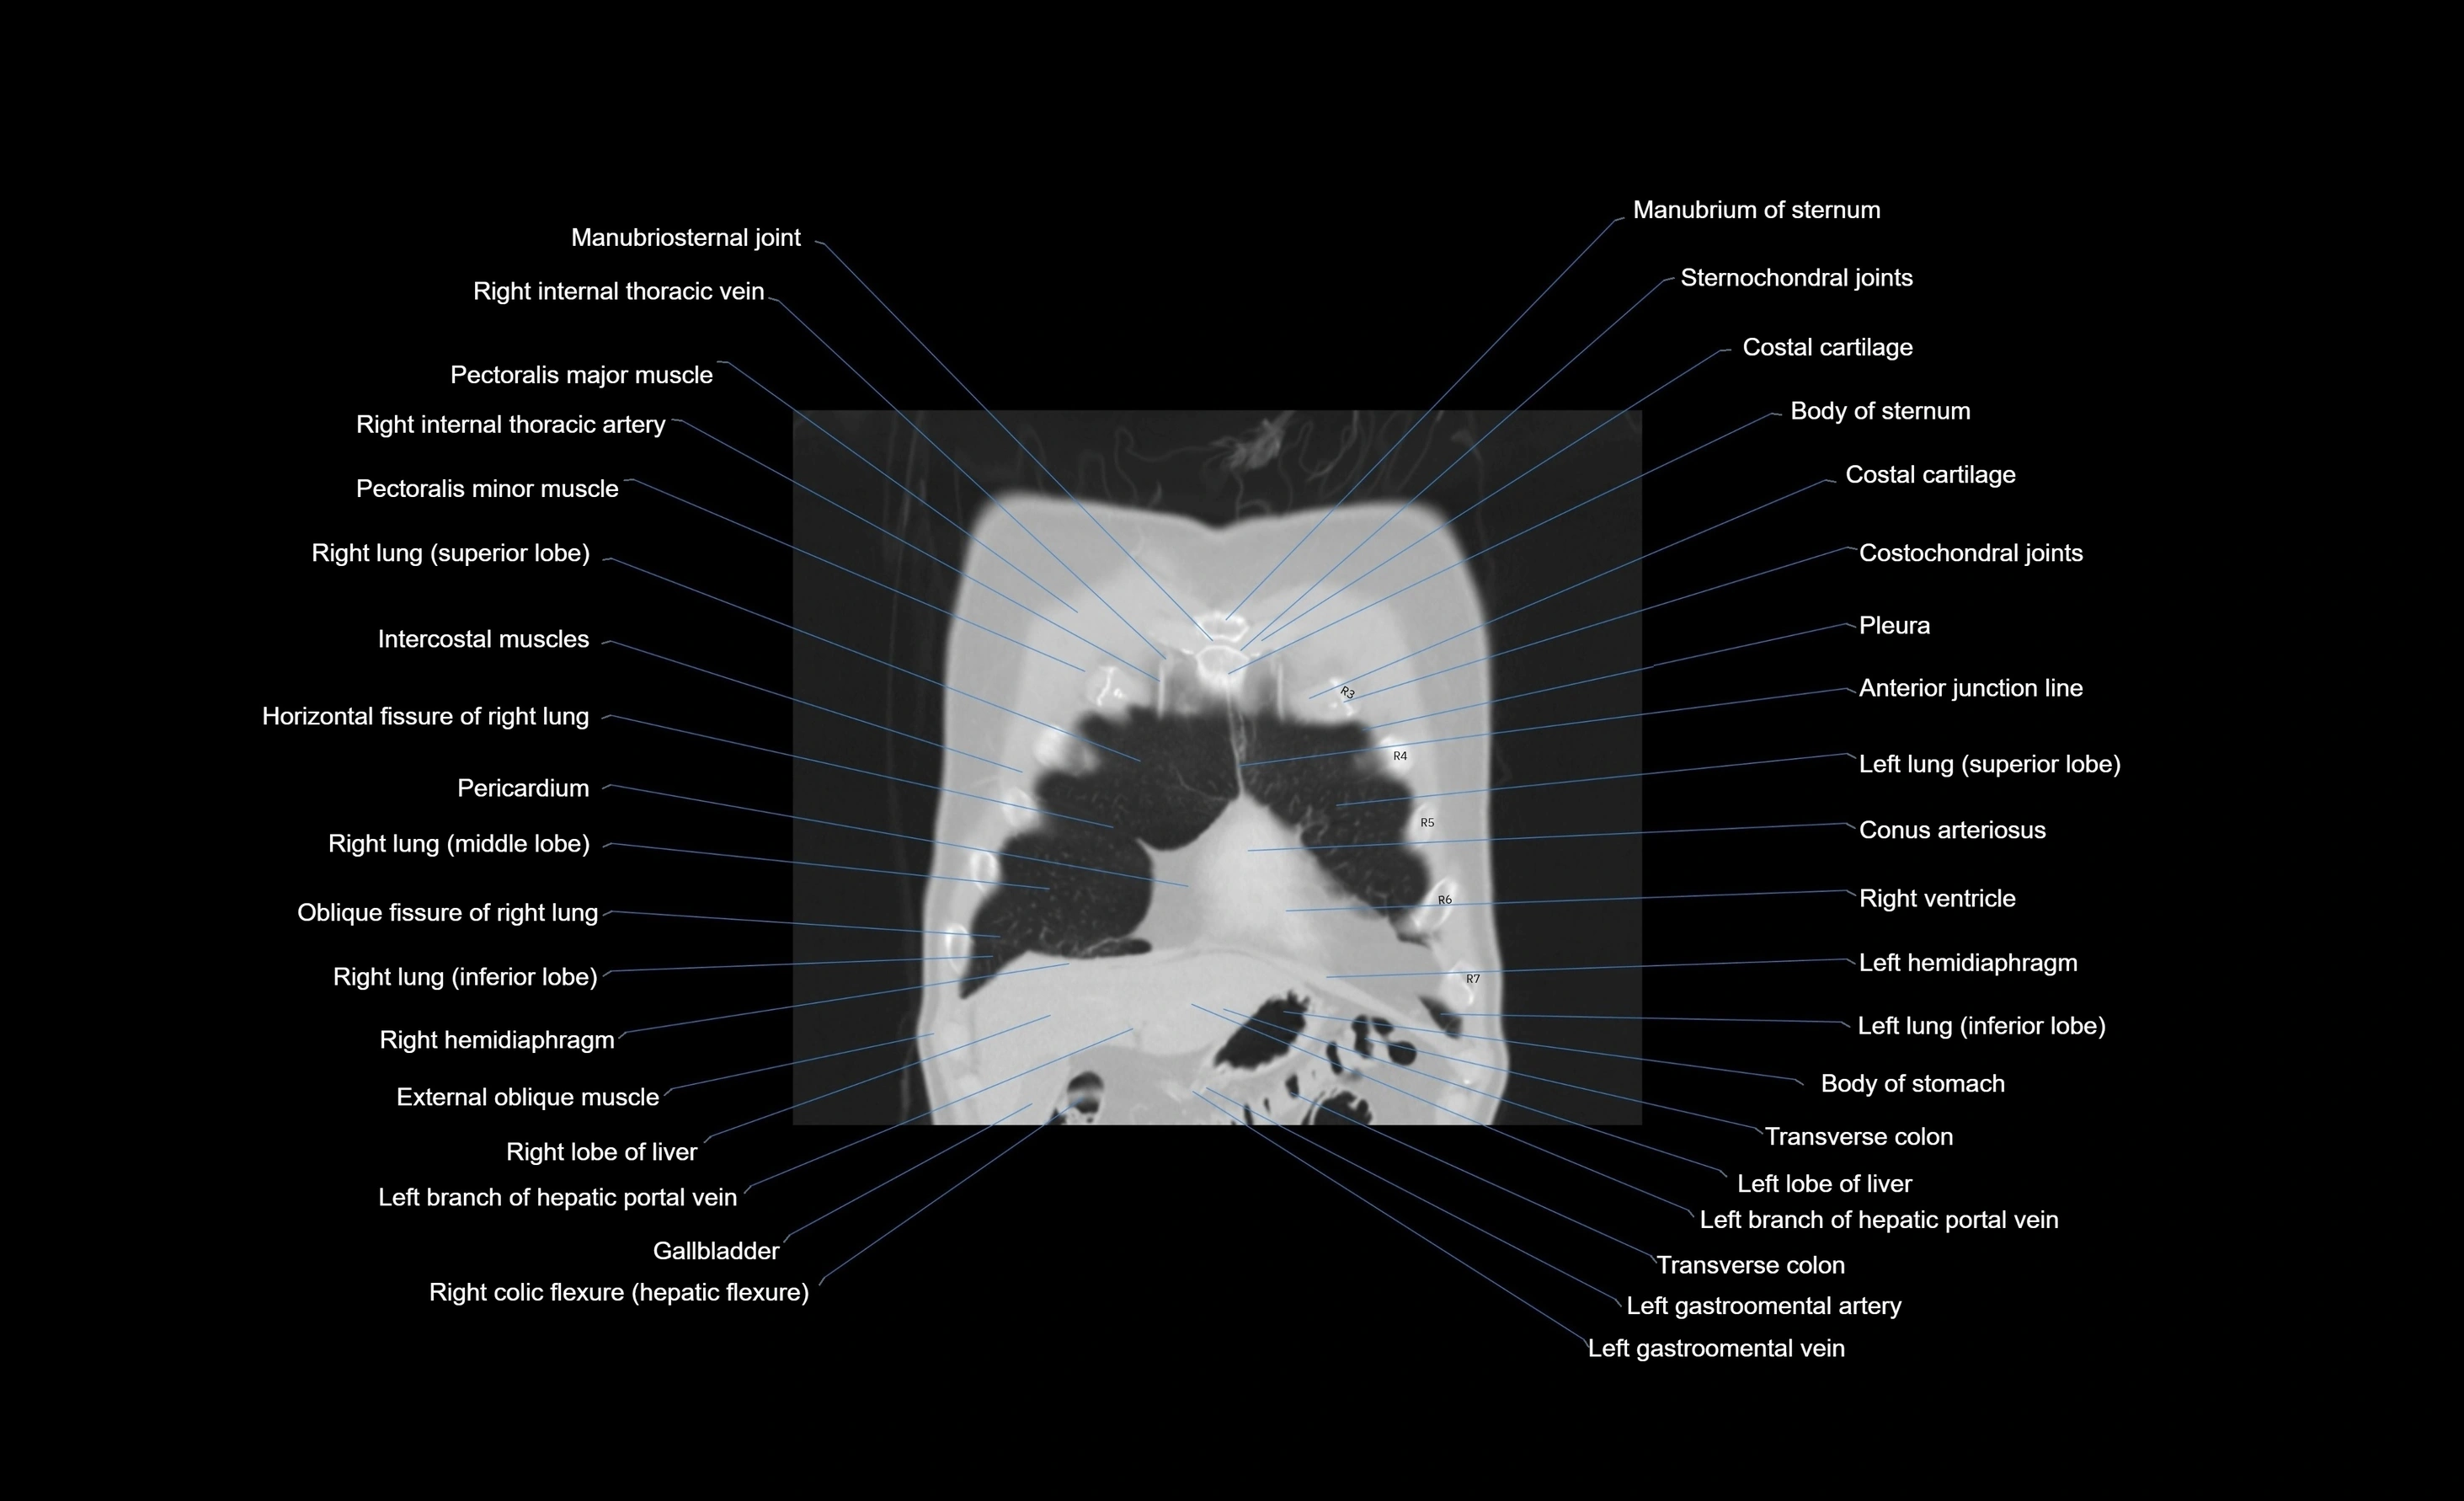

CT images